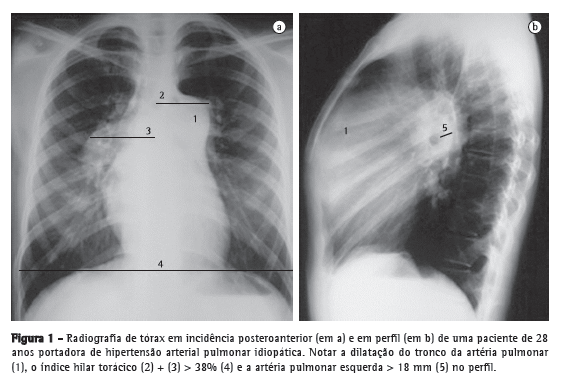

Bastante estudada, a angio-TC conquistou um amplo espaço na avaliação do TEP agudo, tornando-se um exame tão acurado quanto à angiografia pulmonar, mas desprovido do caráter invasivo. Uma série de estudos coloca a angio-TC como a primeira modalidade diagnóstica de imagem no estudo do TEP agudo.(34-36) O motivo está nas suas diversas vantagens: sua alta resolução permite a visualização de artérias e falhas de enchimento até a porção distal da vasculatura pulmonar, atingindo vasos subsegmentares de 2-3 mm (Figura 6); apresenta ótima concordância interobservador, bastante superior ao estudo cintilográfico; e sua sensibilidade é tão alta que um exame negativo pode indicar a suspensão de terapia anticoagulante com segurança.(37)